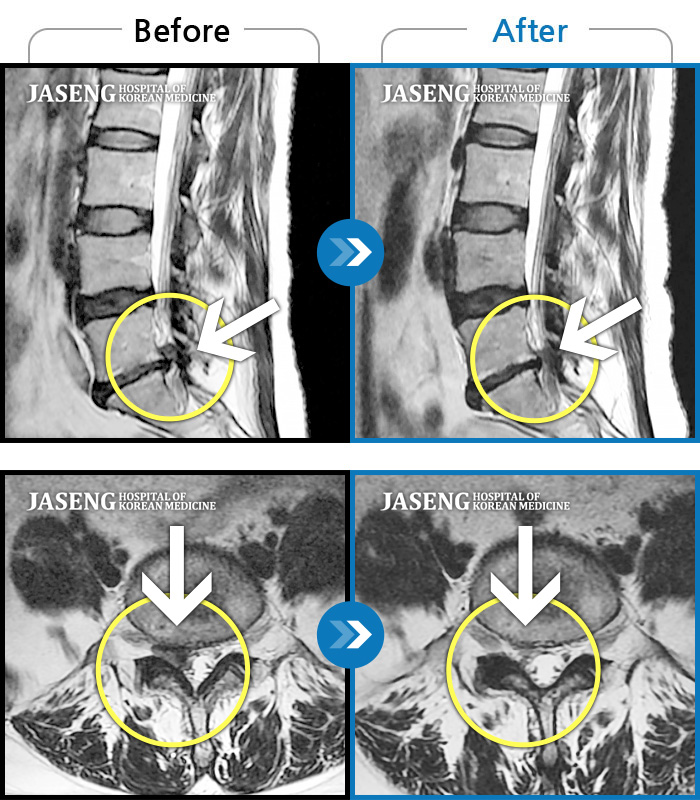

MRI 치료사례

우측 허리 엉덩이부터 다리 당김, 통증